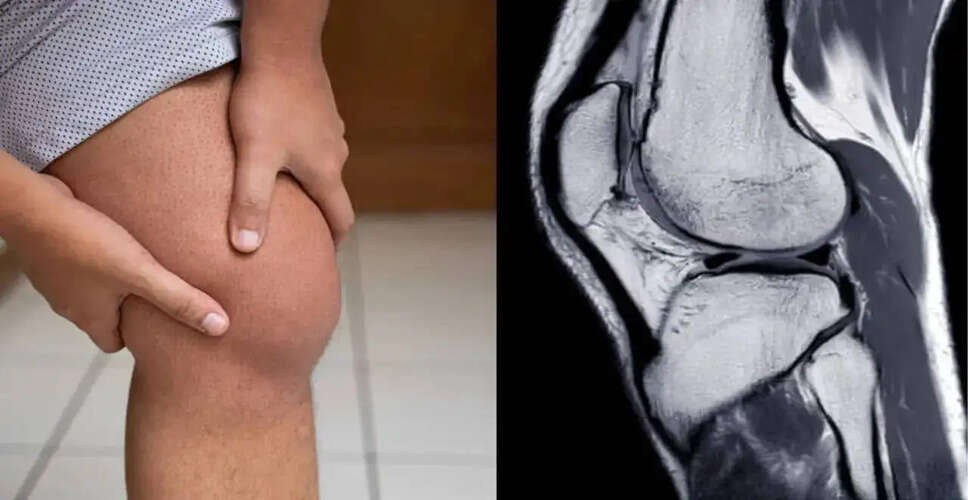

Swelling in the knee without any visible injury is frequently overlooked, with many believing it will resolve naturally. However, recurring swelling may indicate a condition known as Knee Effusion, characterized by an accumulation of excess fluid in or around the knee joint. Recognizing this condition is vital, as early intervention can avert long-term complications and joint deterioration. Dr. Rajeev Verma, Chairman at the Manipal Institute of Bone & Joints, emphasizes that this fluid buildup is often gradual and serves as a signal from the body that something within the knee—be it irritation, inflammation, or another issue—requires attention.

Knee effusion, commonly referred to as joint effusion or a 'swollen knee,' occurs when fluid accumulates in the joint space, resulting in a visibly enlarged and puffy knee. While it primarily affects the knee, other joints such as the ankle, elbow, or shoulder can also be impacted. Symptoms of knee effusion typically include:

- Imaging tests such as X-rays or MRI scans